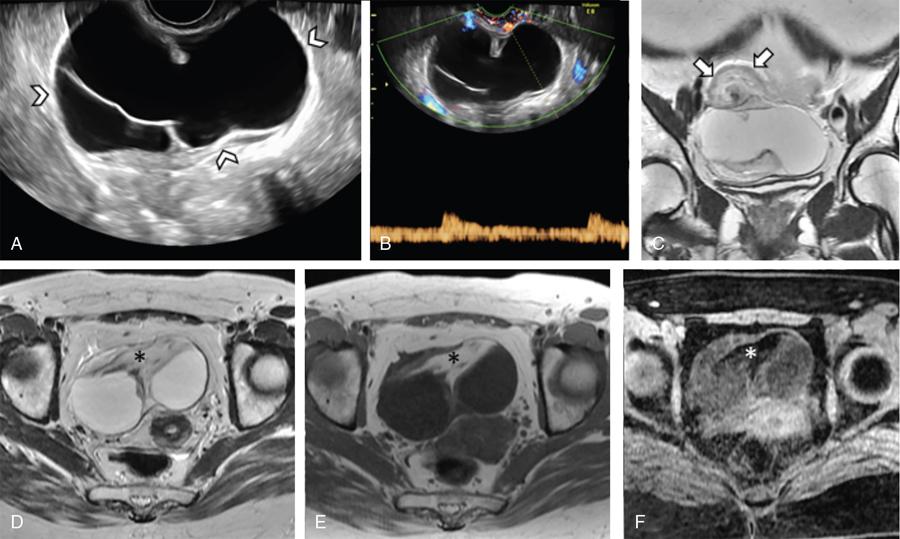

Fig. 11.16.1.4 Adnexal torsion without mass lesion: (A) Grey-scale USG in an adolescent girl with symptoms of acute pelvic pain, nausea and vomiting shows an enlarged right ovary (arrowheads) with heterogeneous stoma and multiple small follicle. (B and C) Colour flow imaging shows arterial flow within the pedicle (curved arrows), but absent intraovarian vascularity. (D) Sagittal, (E) coronal, (F) axial T2WI and (G) GRE confirms the enlarged right ovary with haemorrhagic stroma and small follicles, situated within the pouch of Douglas in the midline (short thick arrows). Note the thickened right pedicle including the fallopian tube (long thin black arrows). Detorsion with oophoropexy was performed.